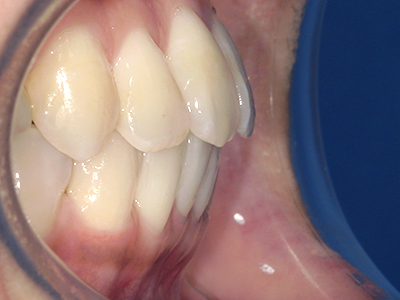

歯並びやかみ合わせを正しく整えると、笑顔や発音の自信につながり、むし歯・歯周病・口臭の予防にも役立ちます。

【4】矯正治療

矯正装置を装着し、調整しながら少しずつ歯を移動させ、歯並びを整えていきます。